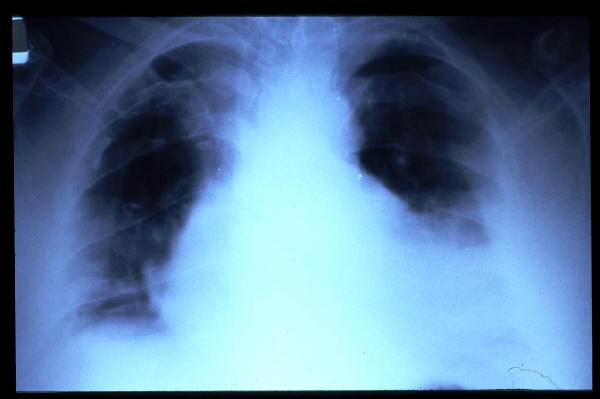

Fibrosis pulmonar. ICC.